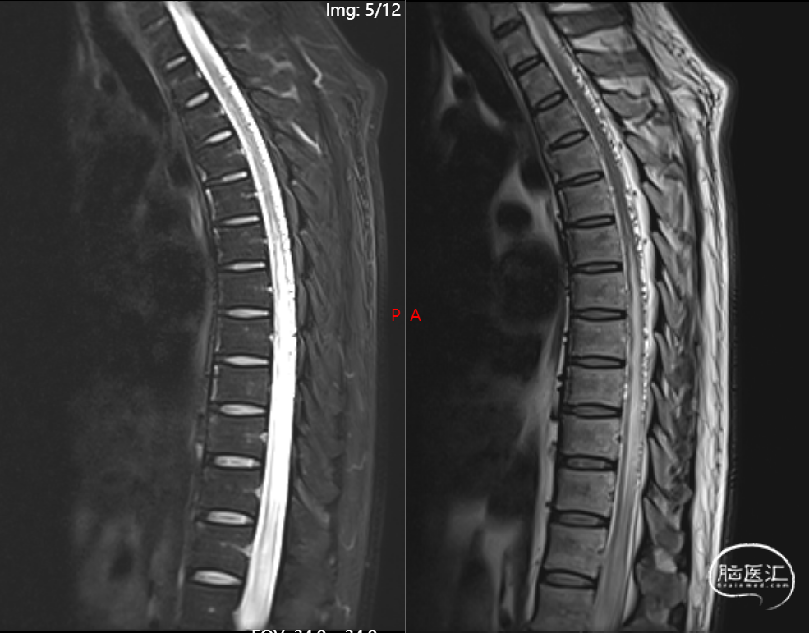

术前影像(2024-02-20, 脊髓血管造影)

image.png

· 通过胸腰椎MRI检查大多可见到血管流空影,进一步脊髓血管造影可以明确诊断。